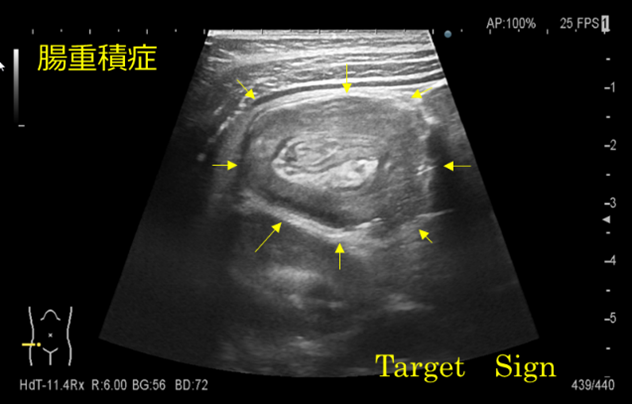

腸重積症とは

腸管の一部が肛門側の腸管内に嵌入することで発生します。

通過障害、血行障害を伴い、複雑性イレウスを引き起こすことがあります。